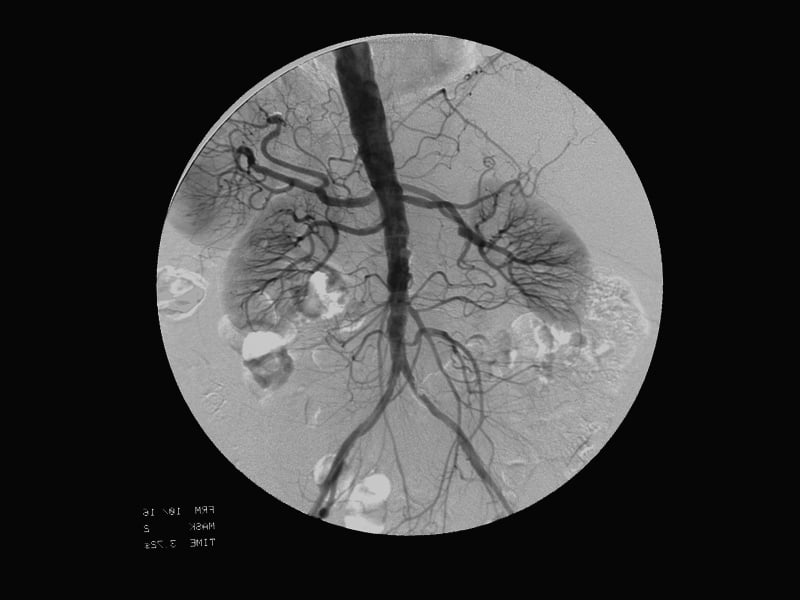

Cardiovascular-interventional procedures use sophisticated imaging techniques to help guide catheters, filters, stents, or other tools or devices through the body. Using these methods, diseases can be treated without surgery.

Cardiovascular-interventional image / Image © ASRT

Cardiovascular-interventional image

Image © ASRT